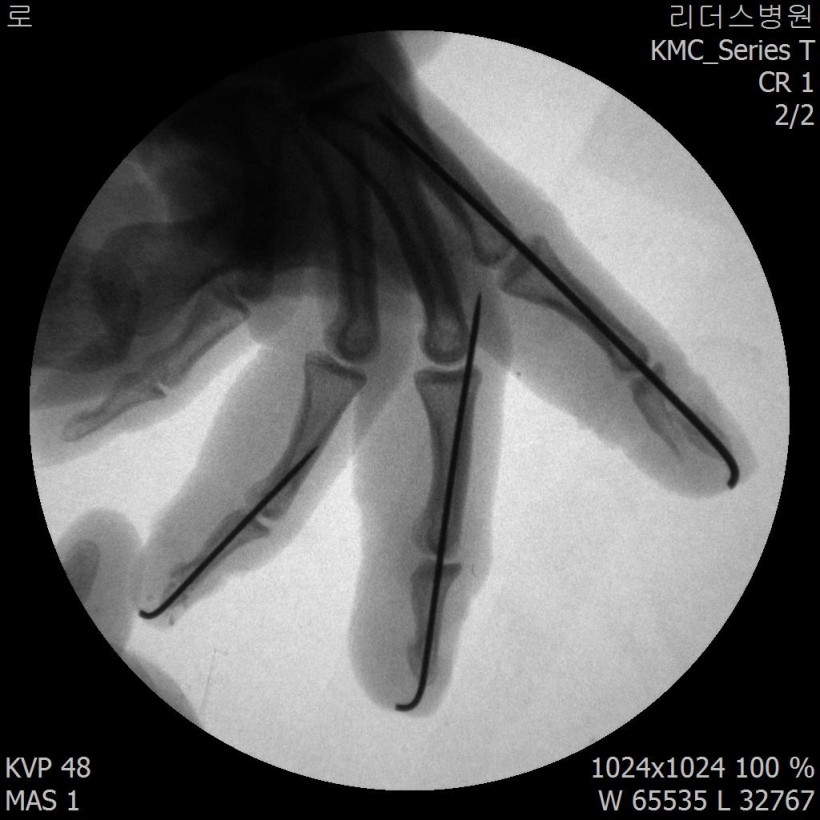

2018, 1월 1일 수지접합 ( 좌측 2,3,4수지 말단전달 치료 전, 후 모습)

2018 / 11일 당시 ( 외국인 로 **)께서 좌측 2,3,4수지 말단전달본원 방문하여